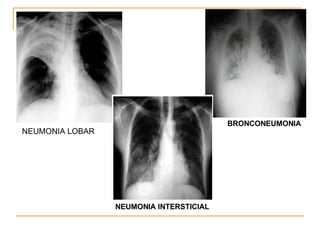

NEUMONIA LOBAR  NEUMONIA INTERSTICIAL BRONCONEUMONIA

Patrón focal  o lobar o Segmentaria Unifocal Multifocal  (prototipo: neumococo) patron multifocal  o bronconeumonía Neumonía Lobulillar  (prototipo: estafilococo) patron intersticial  (focal o difusa): (prot: mycoplasma) patron redonda u oval (niños) Patrones radiológicos(neumonias): patrones  No complicadas comunes

Patrón focal o lobar Afecta a un lóbulo del pulmón   Producida por el neumococo   Las lesiones alveolares localizadas tienen tendencia a la distribución lobar o segmentaria Se extienda a la pleura   densidad  homogénea que oblitera las marcas vasculares normales   está limitada por las cisuras

Apariencia de un lóbulo expandido   Puede acompañarse o no de broncograma aéreo   Organismos que causan más frecuentemente neumonía lobar son el Estreptococo Pneumoniae (fig. 1a) y la Klebsiella Pneumoniae   Klebsiella Pneumoniae   : tiende a seguir un curso más agresivo, produciendo necrosis tisular con cavitación.

Bronconeumonía   Se produce una intensa inflamación en las vías aéreas y el parénquima pulmonar contiguo Opacidades en parches de contornos poco definidos que ocupan mas de un lóbulo   todo un pulmón o de forma bilateral   Puede estar presente el broncograma aéreo   Puede originarse con diversos organismos, aunque el más habitual son las bacterias. Es fácil que se origine después de haber sufrido un resfriado

Patrón intersticial   Se caracteriza por la existencia de líneas o rayas en el parenquima pulmonar   Patrón lineal o linfangítico, que corresponden al engrosamiento de los septos interlobulillares infiltrado  intersticial  inflamatorio y depósito anómalo de fibras del tejido conectivo que pueden conducir a una fibrosis pulmonar que a su vez puede evolucionar hacia un patrón en pana l